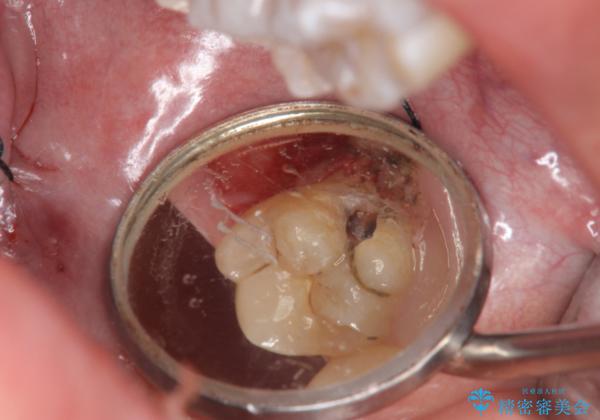

奥歯の虫歯 特殊な形をした歯の治療

- 奥歯が虫歯になり、位置的に詰め物は難しかったため、被せものにする治療を行いました。

頬側に咬頭が一つ多い歯であったのと、歯肉に近い位置が虫歯になっていたため、被せものでしっかり覆う治療を行いました。